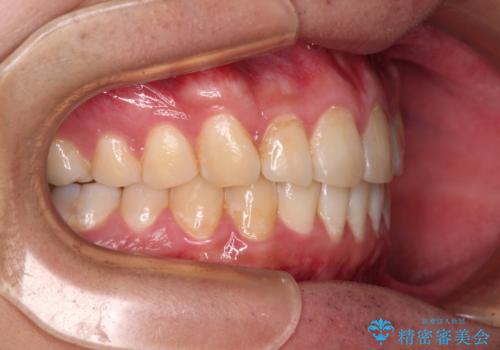

- 上下前歯のデコボコを気にして来院された患者様です。

前歯のデコボコ以外に左側の奥歯の咬み合わせに問題がありましたが、価格を抑え、短期間で気になる前歯を治したいとのことでした。

写真より左側臼歯の咬合がタイトではないことが分かりますが、こちらは保定期間に徐々に咬合させていくこととしました。